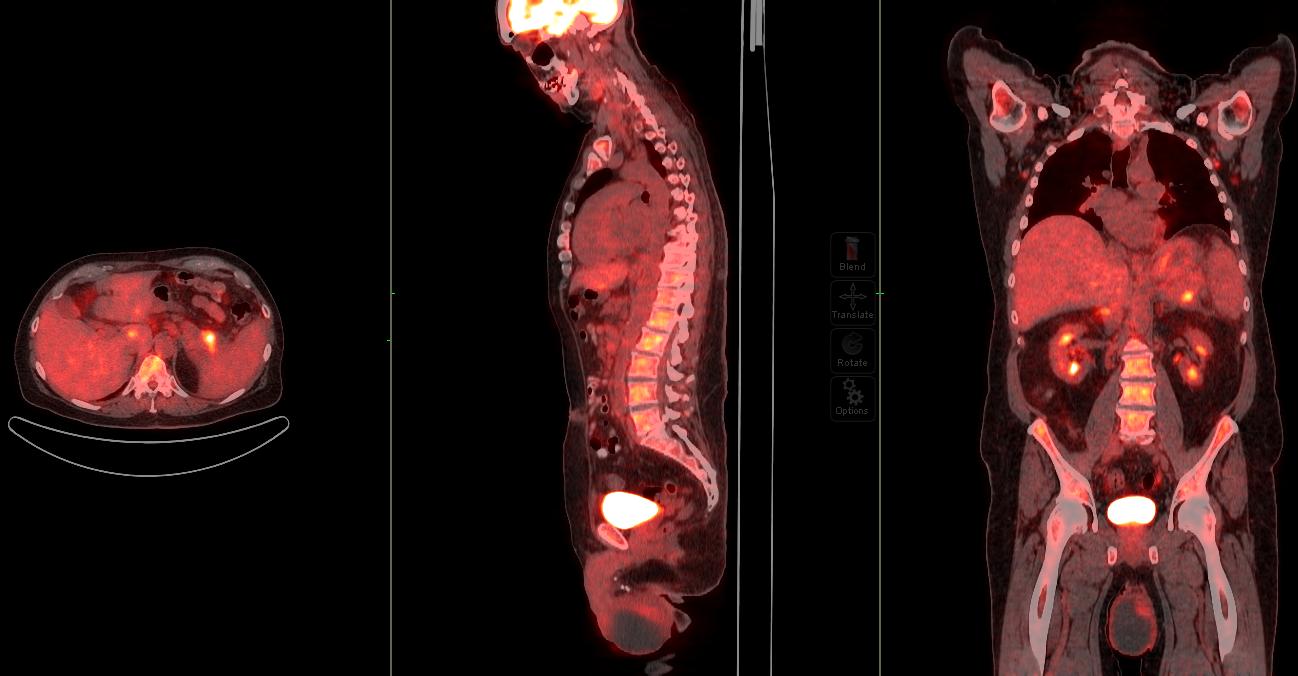

Image: PET/CT scan showing extensive FDG-avid tumor featuring.

PET/CT scan showing extensive FDG-avid tumor featuring